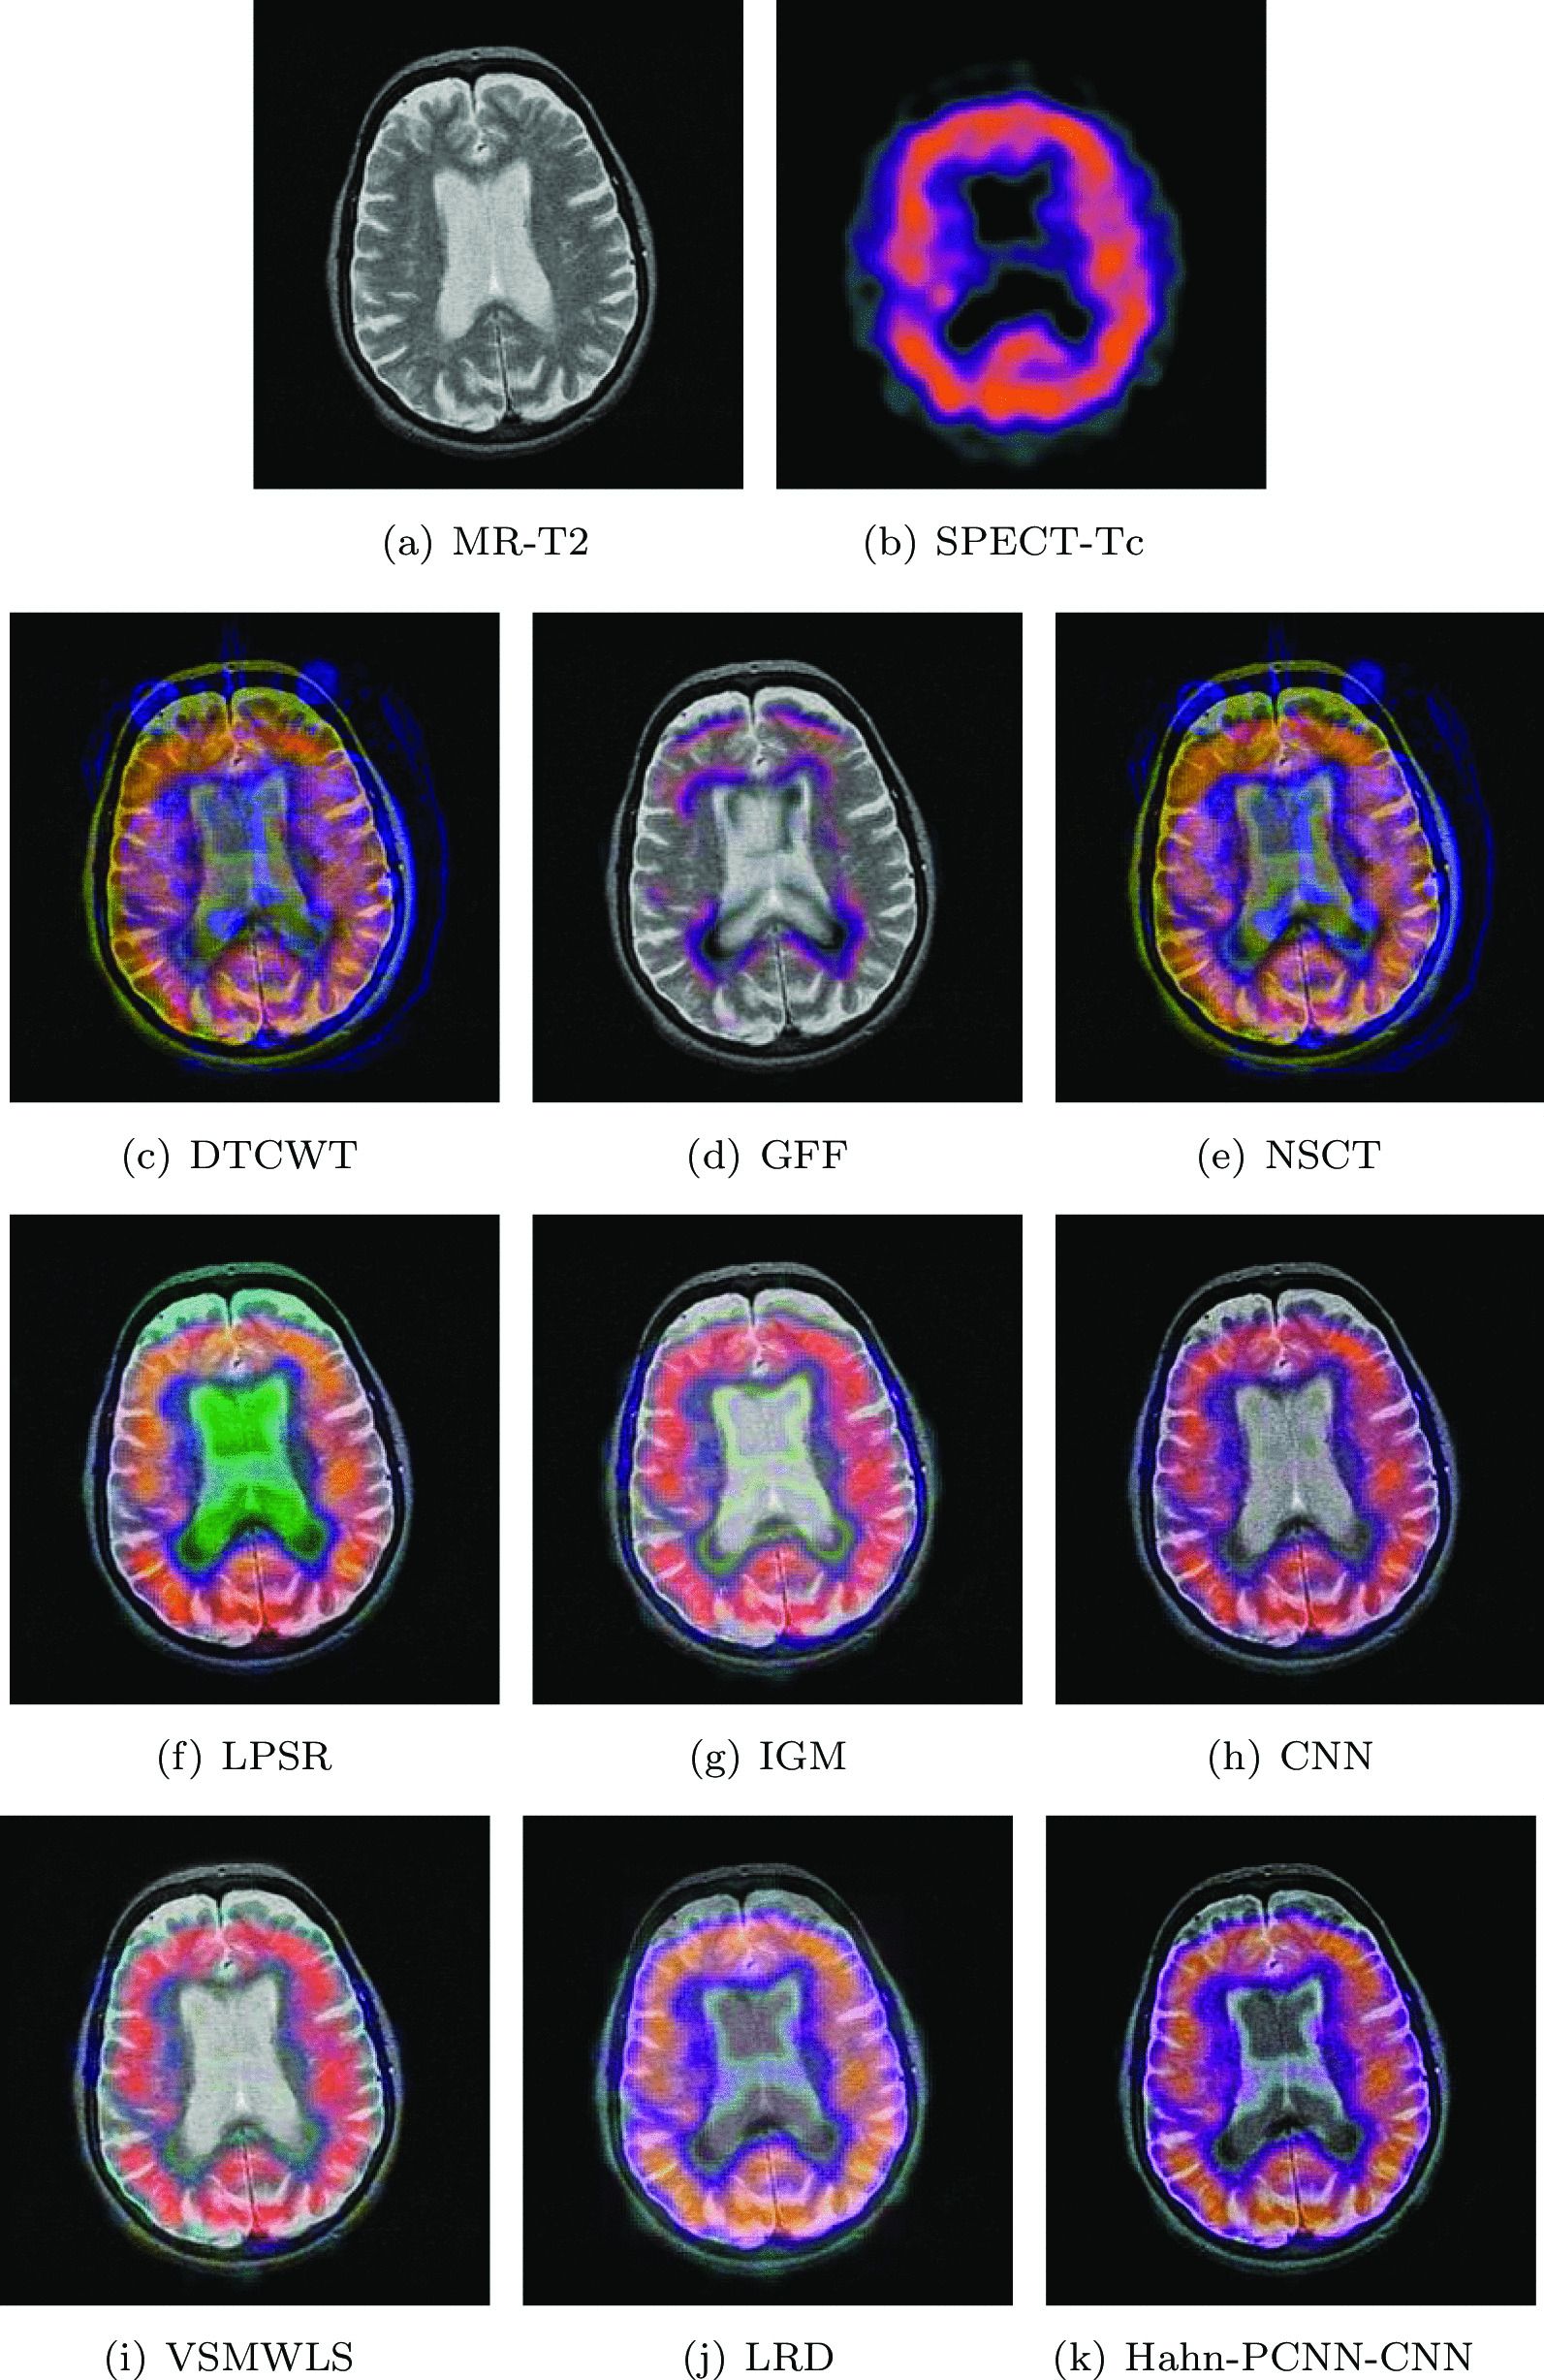

Glioma

The source images in Figs. 4 and 5 are from a 51-year-old female. She has right hemiplegia and hemianopia due to glioma. In the MR-T2 image, the astrocytoma is located in the left parietal lobe; in the SPECT-T1 image, its metabolism is abnormal. Ideally, the fused image should contain both clear astroglioma texture and edges, as well as its metabolism. From Figs. 4 and 5, it can be seen that the fused images obtained based on GFF, IGM and VSMWLS algorithms have better structural information, however, the metabolic state of the tissue can not be obtained. The contrast of the fused image obtained by DTCWT and NSCT algorithms is too low, which causes the image to darken and is not suitable for observation. The fused image obtained based on the CNN algorithm has good structural information and metabolic status, however, the texture and edges of astrogliomas are poor. The fused image obtained by the LPSR algorithm is seriously distorted. Although the fusion image obtained based on the LRD algorithm retains the color information and structural information of the source image well, it is seriously blurred in the diseased tissue, which is not conducive to the diagnosis of the doctor. In general, whether it is normal tissue or glioma, the fused image obtained by our algorithm is the best in preserving structural information and metabolism. Tables 3 and 4 show the quantitative analysis of all fusion algorithms. Obviously, our algorithm performs well in terms of feature mutual information, spatial frequency and cross entropy. Among other metrics, it is also slightly better than other algorithms.

Fig. 4.

The first set of fused MRI-SPECT images from 9 methods on glioma

Fig. 5.

The second set of fused MRI-SPECT images from 9 methods on glioma